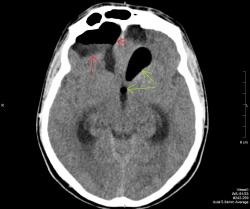

На снимках виден большой костный дефект (желтая стрелка) в задней стенке лобной пазухи, в полости черепа воздух, который прослеживается в области дефекта в полюсе лобной доли, в большой порэнцефалической кисте с уровнем жидкость-воздух (красные стрелки). Киста связана в передним рогом бокового желудочка, в противоположном желудочке и в третьем воздух (зеленые стрелки). На сагиттальных срезах виден воздух в мостовой цистерне вдоль ската. Поскольку дефект довольно большой, сейчас решается вопрос как лучше его закрыть эндоскопически или через трепанацию.